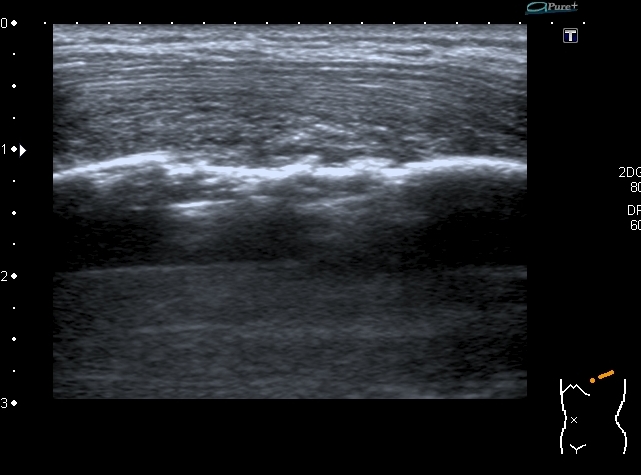

Деструкция корткального слоя 7-го ребра с ткаенвым компонетом, исходящим из кости. 7th rib destruction with solid mass

Поперечный скан. Transverse scan

образование оттесняет сосуд,  в самом кровоток достоверно не определяется. No bloodflow in mass is detected.